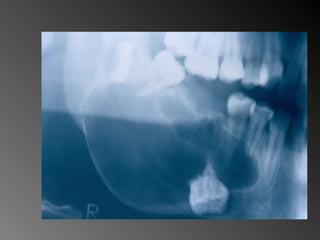

26 - Pacientedo sexo feminino, 30 anos de idade, se apresentou com aumento de volume no corpo da mandíbula, região dos dentes 45, 46 e 47, assintomático e com evolução de aproximadamente 1 ano. Pelo exame clínico constatamos expansão óssea e deslocamento dos dentes 45 e 46 de suas posições normais. Através de radiografia panorâmica observamos uma imagem radiográfica multilocular onde as trabéculas ósseas se encontravam perpendicularmente umas às outras e em outras regiões com aspecto de bolha de sabão. Com base no quadro clínico, o diagnóstico é: a) Ceratocisto e mixoma odontogênico. b) Odontoma composto e ameloblastoma. c) Mixoma odontogênico e ameloblastoma. d) Mixoma odontogênico e odontoma composto. e) Ameloblastoma e ceratocisto.

26 - Paciente do sexo feminino, 30 anos de idade, se apresentou com aumento de volume no corpo da mandíbula, região dos dentes 45, 46 e 47, assintomático e com evolução de aproximadamente 1 ano. Pelo exame clínico constatamos expansão óssea e deslocamento dos dentes 45 e 46 de suas posições normais. Através de radiografia panorâmica observamos uma imagem radiográfica multilocular onde as trabéculas ósseas se encontravam perpendicularmente umas às outras e em outras regiões com aspecto de bolha de sabão. Com base no quadro clínico, o diagnóstico é: a) Ceratocisto e mixoma odontogênico. b) Odontoma composto e ameloblastoma. c) Mixoma odontogênico e ameloblastoma. d) Mixoma odontogênico e odontoma composto. e) Ameloblastoma e ceratocisto.

Ameloblastoma Freqüência: -1%de todos os cistos e tumores dos maxilares - Maior ocorrência entre a segunda e a quinta décadas de Vida (picos entre 35 e 45) -80% ocorrem na mandíbula -Área de molares inferiores, ramo ascendente de mandíbula. -Na maxila: molares superiores, seios maxilares e assoalho da fossa nasal (TOMMASI e FERNANDES, 2002)

Mixoma Freqüência:  -Segunda e terceira década de vida -Atinge pouco mais a maxila que a mandíbula (região posterior + frequente)

Ameloblastoma Freqüência: -1% de todos os cistos e tumores dos maxilares - Maior ocorrência entre a segunda e a quinta décadas de  Vida (picos entre 35 e 45)  -80% ocorrem na mandíbula -Área de molares inferiores, ramo ascendente de  mandíbula.  -Na maxila: molares superiores, seios maxilares e assoalho  da fossa nasal  (TOMMASI e FERNANDES, 2002)